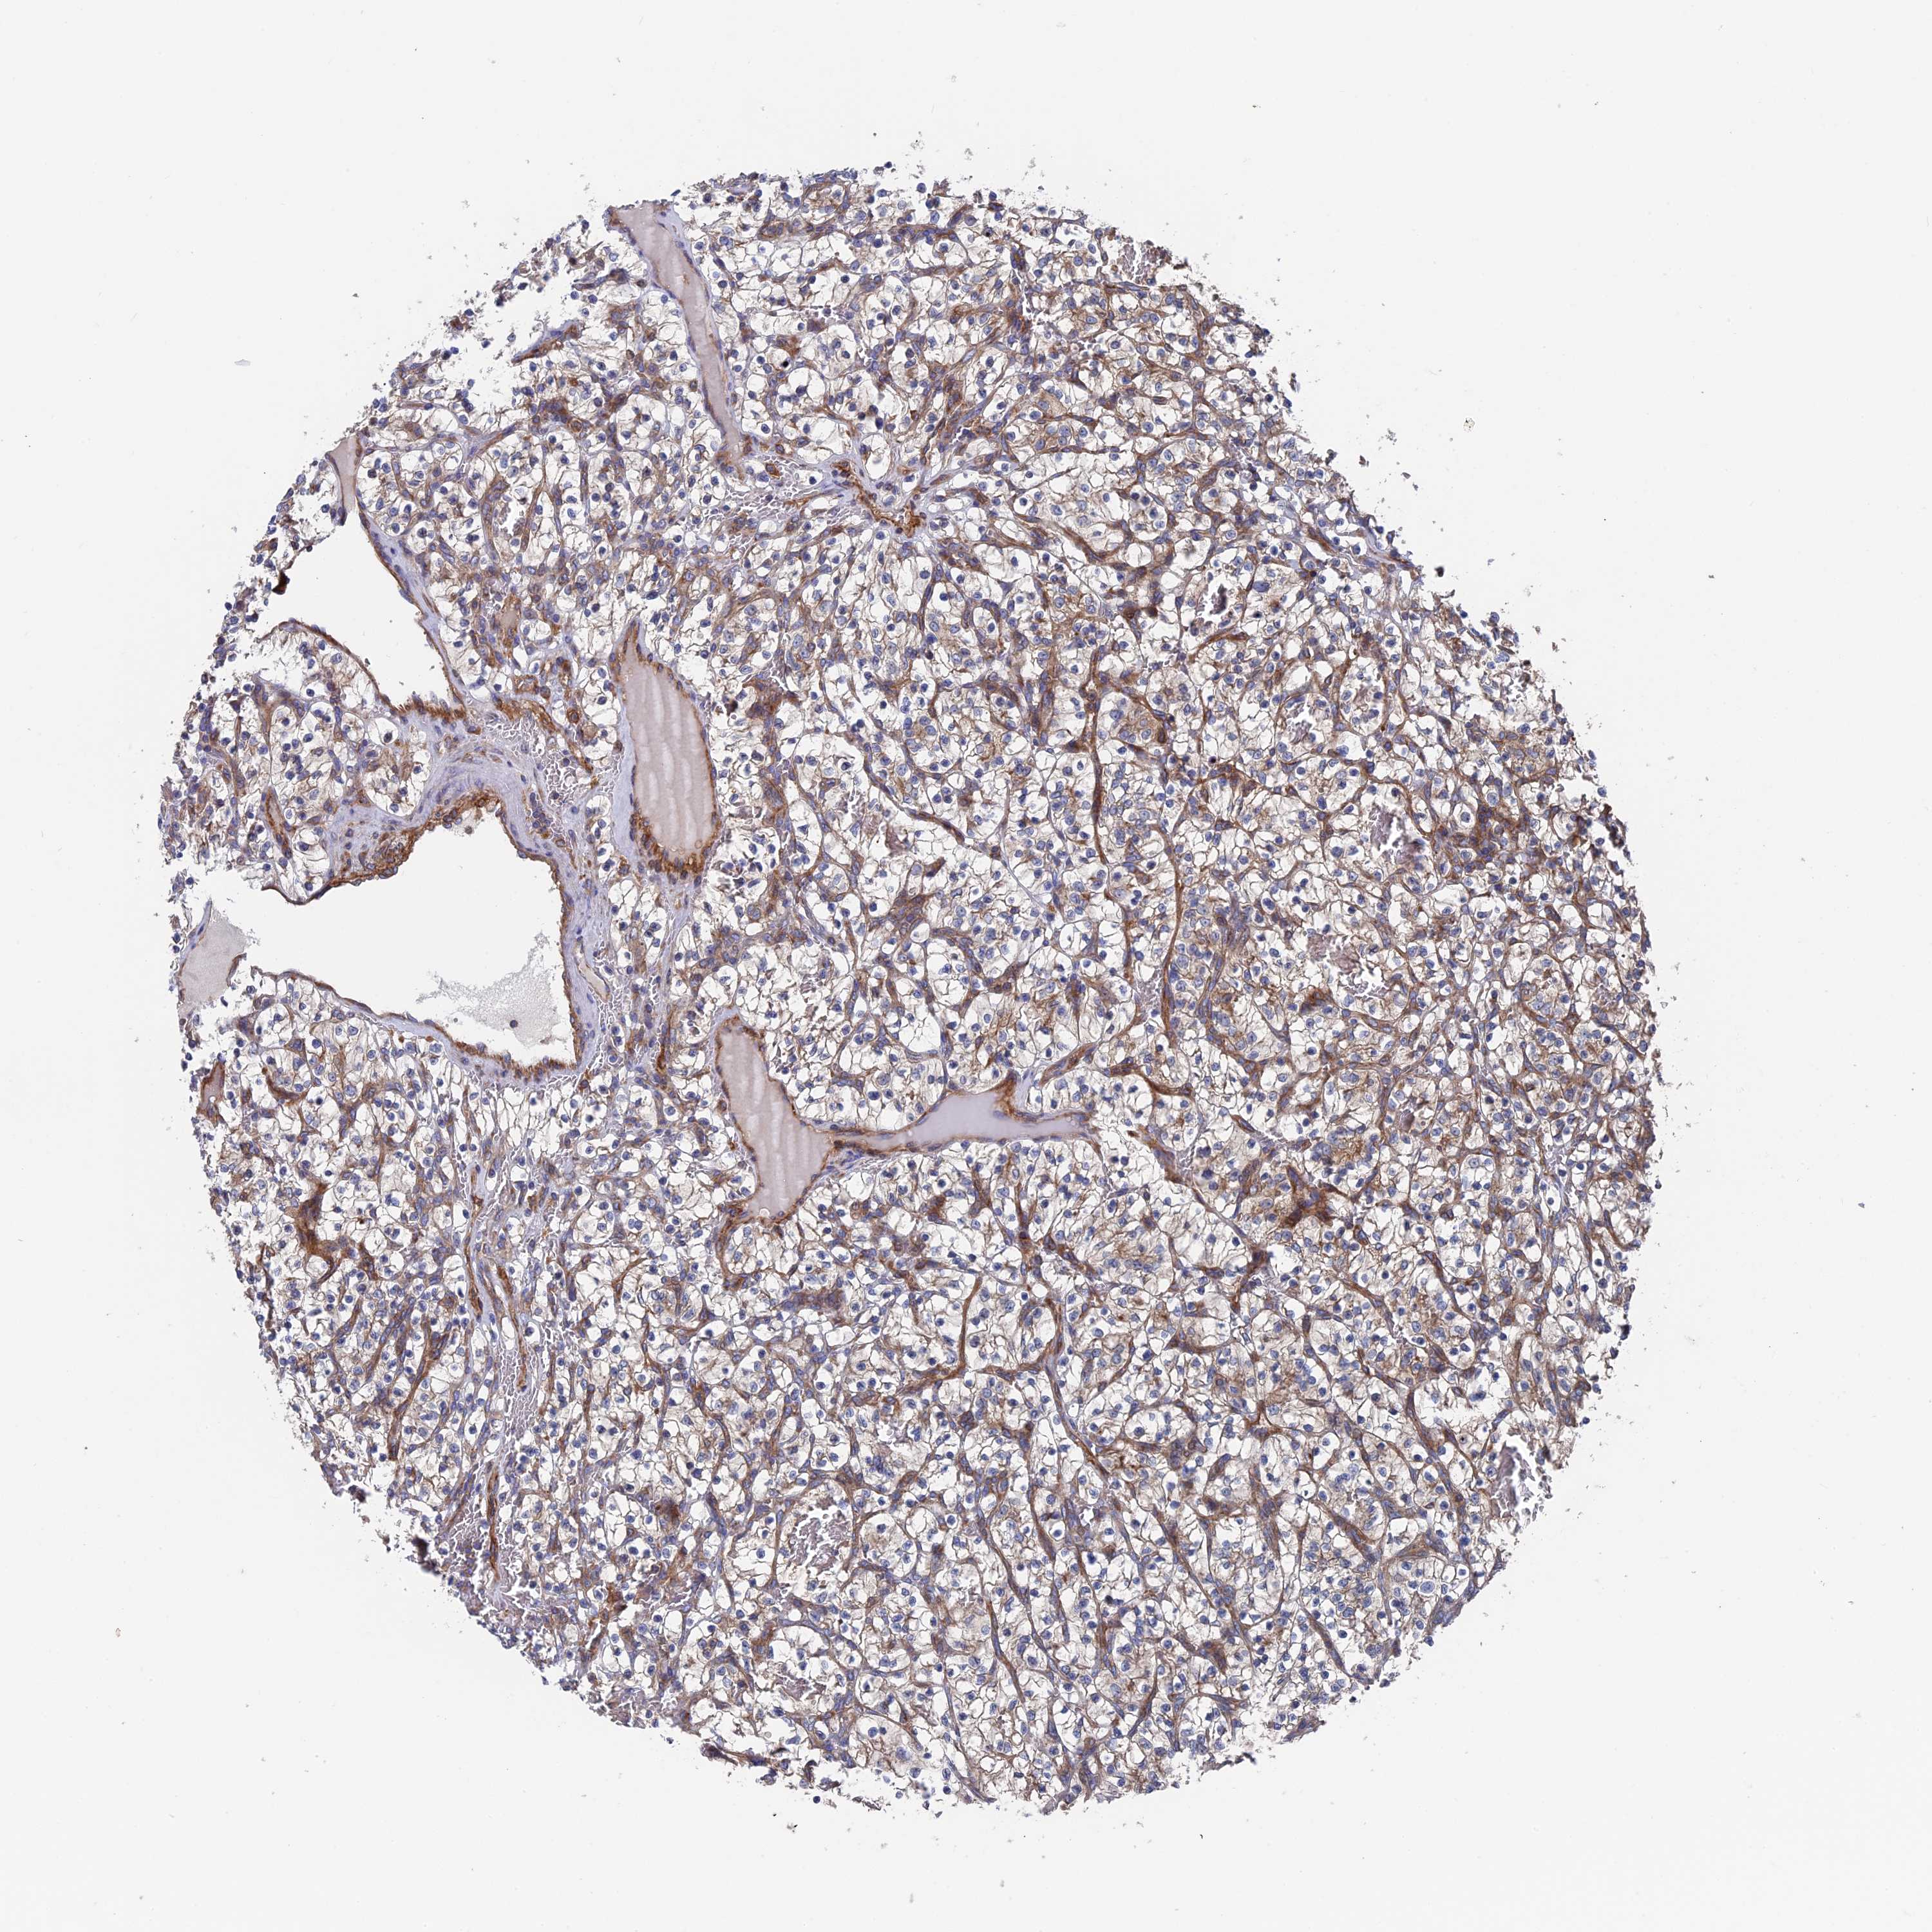

KIDNEY RENAL CLEAR CELL CARCINOMA (VALIDATION) - Interactive survival scatter ploti

The Survival Scatter plot shows the clinical status (i.e. dead or alive) for all individuals in the patient cohort, based on the same data that underlies the corresponding Kaplan-Meier plots. Patients that are alive at last time for follow-up are shown in blue and patients who have died during the study are shown in red.

The x-axis shows the expression levels (FPKM) of the investigated gene in the tumor tissue at the time of diagnosis. The y-axis shows the follow-up time after diagnosis (years). Both axes are complimented with kernel density curves demonstrating the data density over the axes. The top density plot shows the expression levels (FPKM) distribution among dead (red) and alive patients (blue). The right density plot shows the data density of the survived years of dead patients with high and low expression levels respectively, stratified using the cutoff indicated by the vertical dashed line through the Survival Scatter plot. This cutoff is automatically defined based on the FPKM cutoff that minimizes the p-score. The cutoff can be changed by dragging the vertical line or by entering a cutoff value in the square labeled "Current cut-off".

Under the Survival Scatter plot the p-score landscape (black curve; left axis) is shown together with dead median separation (red curve; right axis). Dead median separation is the difference in median mRNA expression between patients who have died with high and low expression, respectively. It is calculated as follows: median FPKM expression of dead patients with high expression - median FPKM expression of dead patients with low expression. This is intended to aid the user in visually exploring custom cutoffs and the associated p-scores and dead median separation.

Individual patient data is displayed and can be filtered by clicking on one or more of the category buttons on the top of the page. Categories describing expression level and patient information include: high, low, alive, dead, female, male and tumor stages. The scale of the x-axis can be toggled between linear and log-scale by clicking on the "x log" button. Mouse-over function shows TCGA ID, patient information and mRNA expression (FPKM) for each patient.

& Survival analysisi

Kaplan-Meier plots summarize results from analysis of correlation between mRNA expression level and patient survival. Patients were divided based on level of expression into one of the two groups "low" (under cut off) or "high" (over cut off). X-axis shows time for survival (years) and y-axis shows the probability of survival, where 1.0 corresponds to 100 percent.

DNAJC3 is not prognostic in Kidney Renal Clear Cell Carcinoma (validation)

Best expression cut offi

Based on the FPKM value of each gene, patients were classified into two groups and association between prognosis (survival) and gene expression (FPKM) was examined. The best expression cut-off refers the FPKM value that yields maximal difference with regard to survival between the two groups at the lowest log-rank P-value. Best expression cut-off was selected based on survival analysis .

When clicking on this number, the vertical dashed line indicating cut-off, the interactive survival plot, and the Kaplan-Meier curve will be adjusted to show results based on the best expression cut-off.

: 42.28

P scorei

Log-rank P value for Kaplan-Meier plot showing results from analysis of correlation between mRNA expression level and patient survival.

N/A

TCGA RNA samplesi

RNA-seq data is reported as average FPKM (number Fragments Per Kilobase of exon per Million reads), generated by the The Cancer Genome Atlas (TCGA) .

Normal distribution across the dataset is visualized with box plots, shown as median and 25th and 75th percentiles. Points are displayed as outliers if they are above or below 1.5 times the interquartile range. FPKM values of the individual samples are presented next to the box plot.

Average pTPM 43.0

Number of samples 100